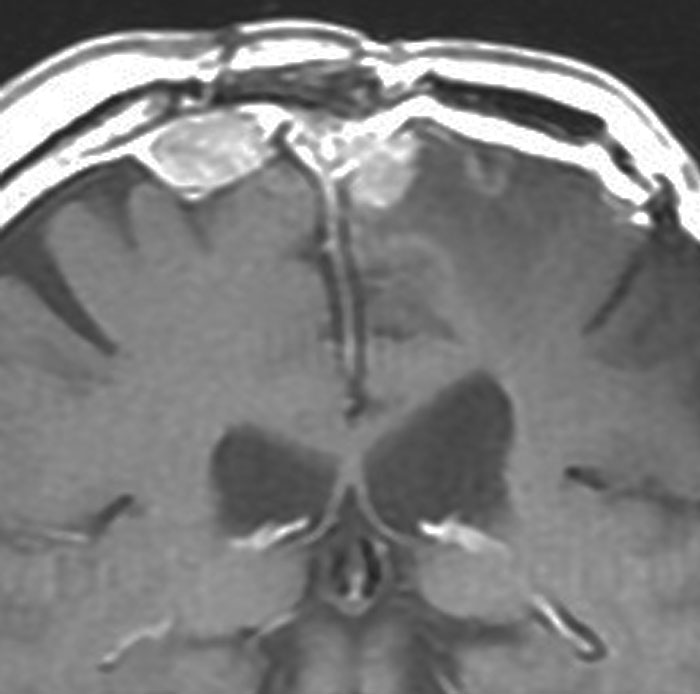

左は,造影剤を使ったガドリニウム増強MRIです。腫瘍が白く丸く見えます。右はフレア画像で,腫瘍の周囲の脳浮腫(脳のはれ)です。左前頭葉が,かなり強くはれています。この腫瘍は小さいのですが,脳のはれが強すぎるので手術摘出したほうがいいです。浮腫が悪化すると,てんかん発作や認知機能低下がでる可能性があります。

典型的な髄膜腫

この髄膜腫は中程度の大きさのものです。円蓋部髄膜種という最も多い最も手術の簡単なタイプです。麻痺や失語症やてんかんなどの症状はありません。とても美しくて若い女性の髄膜腫でしたが,子供に遺伝はしませんし,癌などと違ってタバコなどこれといった原因がなくて発生するものです。

MRIでの髄膜腫の見え方は撮影の仕方によっていろいろです。左からT1強調画像,T2強調画像,フレア画像といいます。腫瘍の横に小さく白い領域がありますが,これは脳の腫れた部分で脳浮腫といいます。髄膜腫があると周囲に脳浮腫が生じることがあります。

最も見やすいのが,ガドリニウム造影剤を注射して撮影するものです。一般的に髄膜腫は造影剤で白く映し出されます。この腫瘍は左脳側にあります。MRIの軸面という輪切りの写真では左右が逆になりますから注意してください。脳を下から見た図になっています。MRIはいろいろな方向から腫瘍を見ることができますが,右は冠状断という正面から見た図です。よく見ると腫瘍の上と下のはじっこに線状に糸を引いたように造影される部分があります。これをテールサイン(しっぽのサイン)といいます。腫瘍が硬膜に沿って延びている可能性があることを示しています。